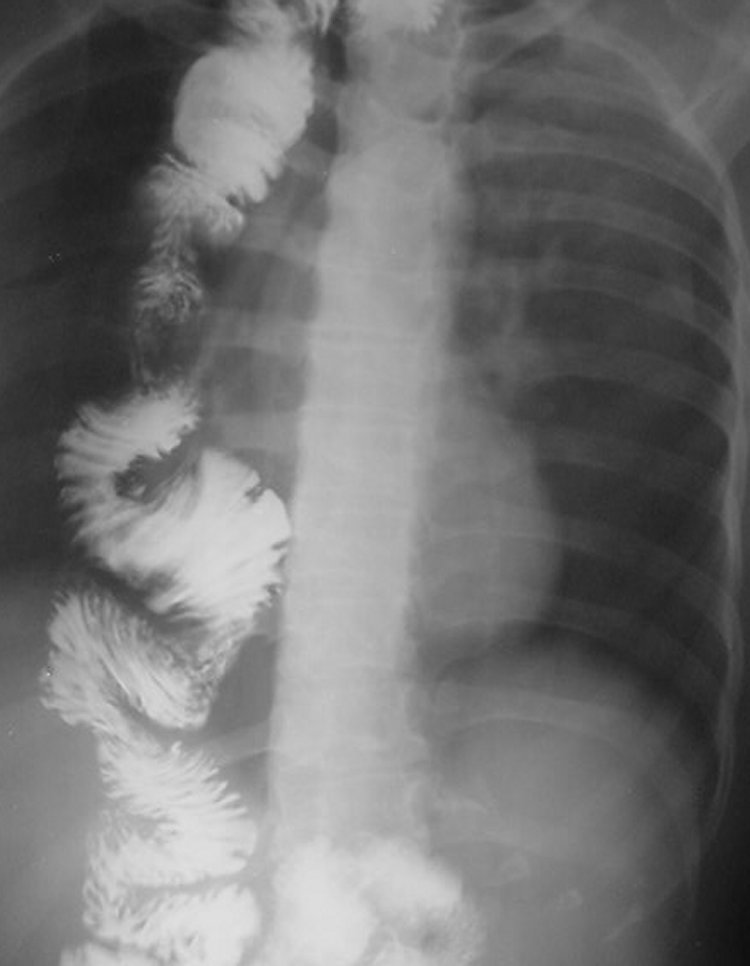

Esofagoplastii cu intestin subțire respectiv colon